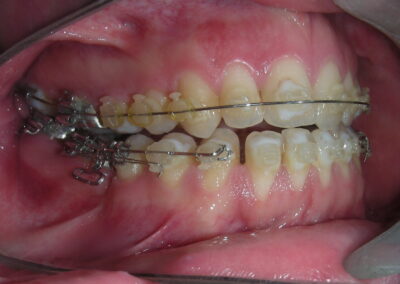

The vertical vector of intrusion was located too far posteriorly to allow for the placement of TADs in that region. At this point, the utility arch developed by Dr. Ricketts was introduced into the mechanics . I referred to as the “Tilting Utility Arch.” made with Blue Elgiloy .017″ × .025″. It was employed as a lever arm to transmit the intrusive force generated by the coil spring and anchored by the TADs.

The upper brackets were bonded solely for the purpose of providing stability to the utility arch . Following the hierarchically structured treatment plan, we proceed with the alignment and leveling phase in order to enable mesialization of the posterior segments using sliding mechanics, which works effectively in conjunction with Roth prescription brackets .022.

A progressive archwire sequence was used for alignment, leveling, and three-dimensional control.

- .018″ × .018″ Blue Elgiloy sectional archwire was placed in three segments in the maxillary arch to maximize the effectiveness of Class II intermaxillary elastics, in conjunction with space closure (mesialization) in the mandibular arch.

- 017″ × .025″ Blue Elgiloy sectional leveling archwire beetwen # 35-37 and 45-47

- 017″ × .025″ Stainless Steel (SS) + Closed-coil NiTi springs were activated between the molars and anterior segment

- 019″ × .025″ Stainless Steel (SS)